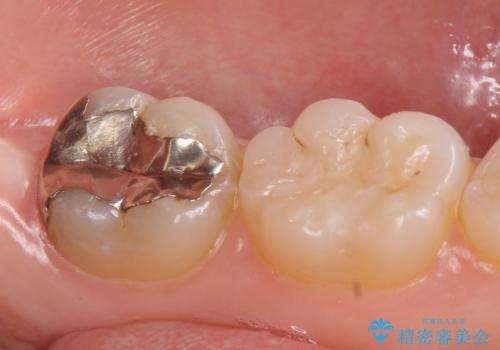

- 左下7の銀歯を白くしたいといらっしゃった方の症例です。

左下7遠心(下記のX線写真の左側)の歯質が歯肉縁下でかつポケットも深かったため、歯茎を下げる歯周外科を行いました。

その後歯茎の治りを待ちポケットが正常値であることを確認後、オールセラミッククラウンによる補綴を行いました。

今回用いたオールセラミッククラウンはジルコニアフレームという白い素材の上にセラミックを盛っているため、審美性が非常に高いのが特徴です。

また、ジルコニアは人工ダイヤモンドの材料にも使われているほど高い強度を持っており、そのためオールセラミッククラウンは審美性だけでなく、奥歯やブリッジの補綴も可能とするクラウンです。